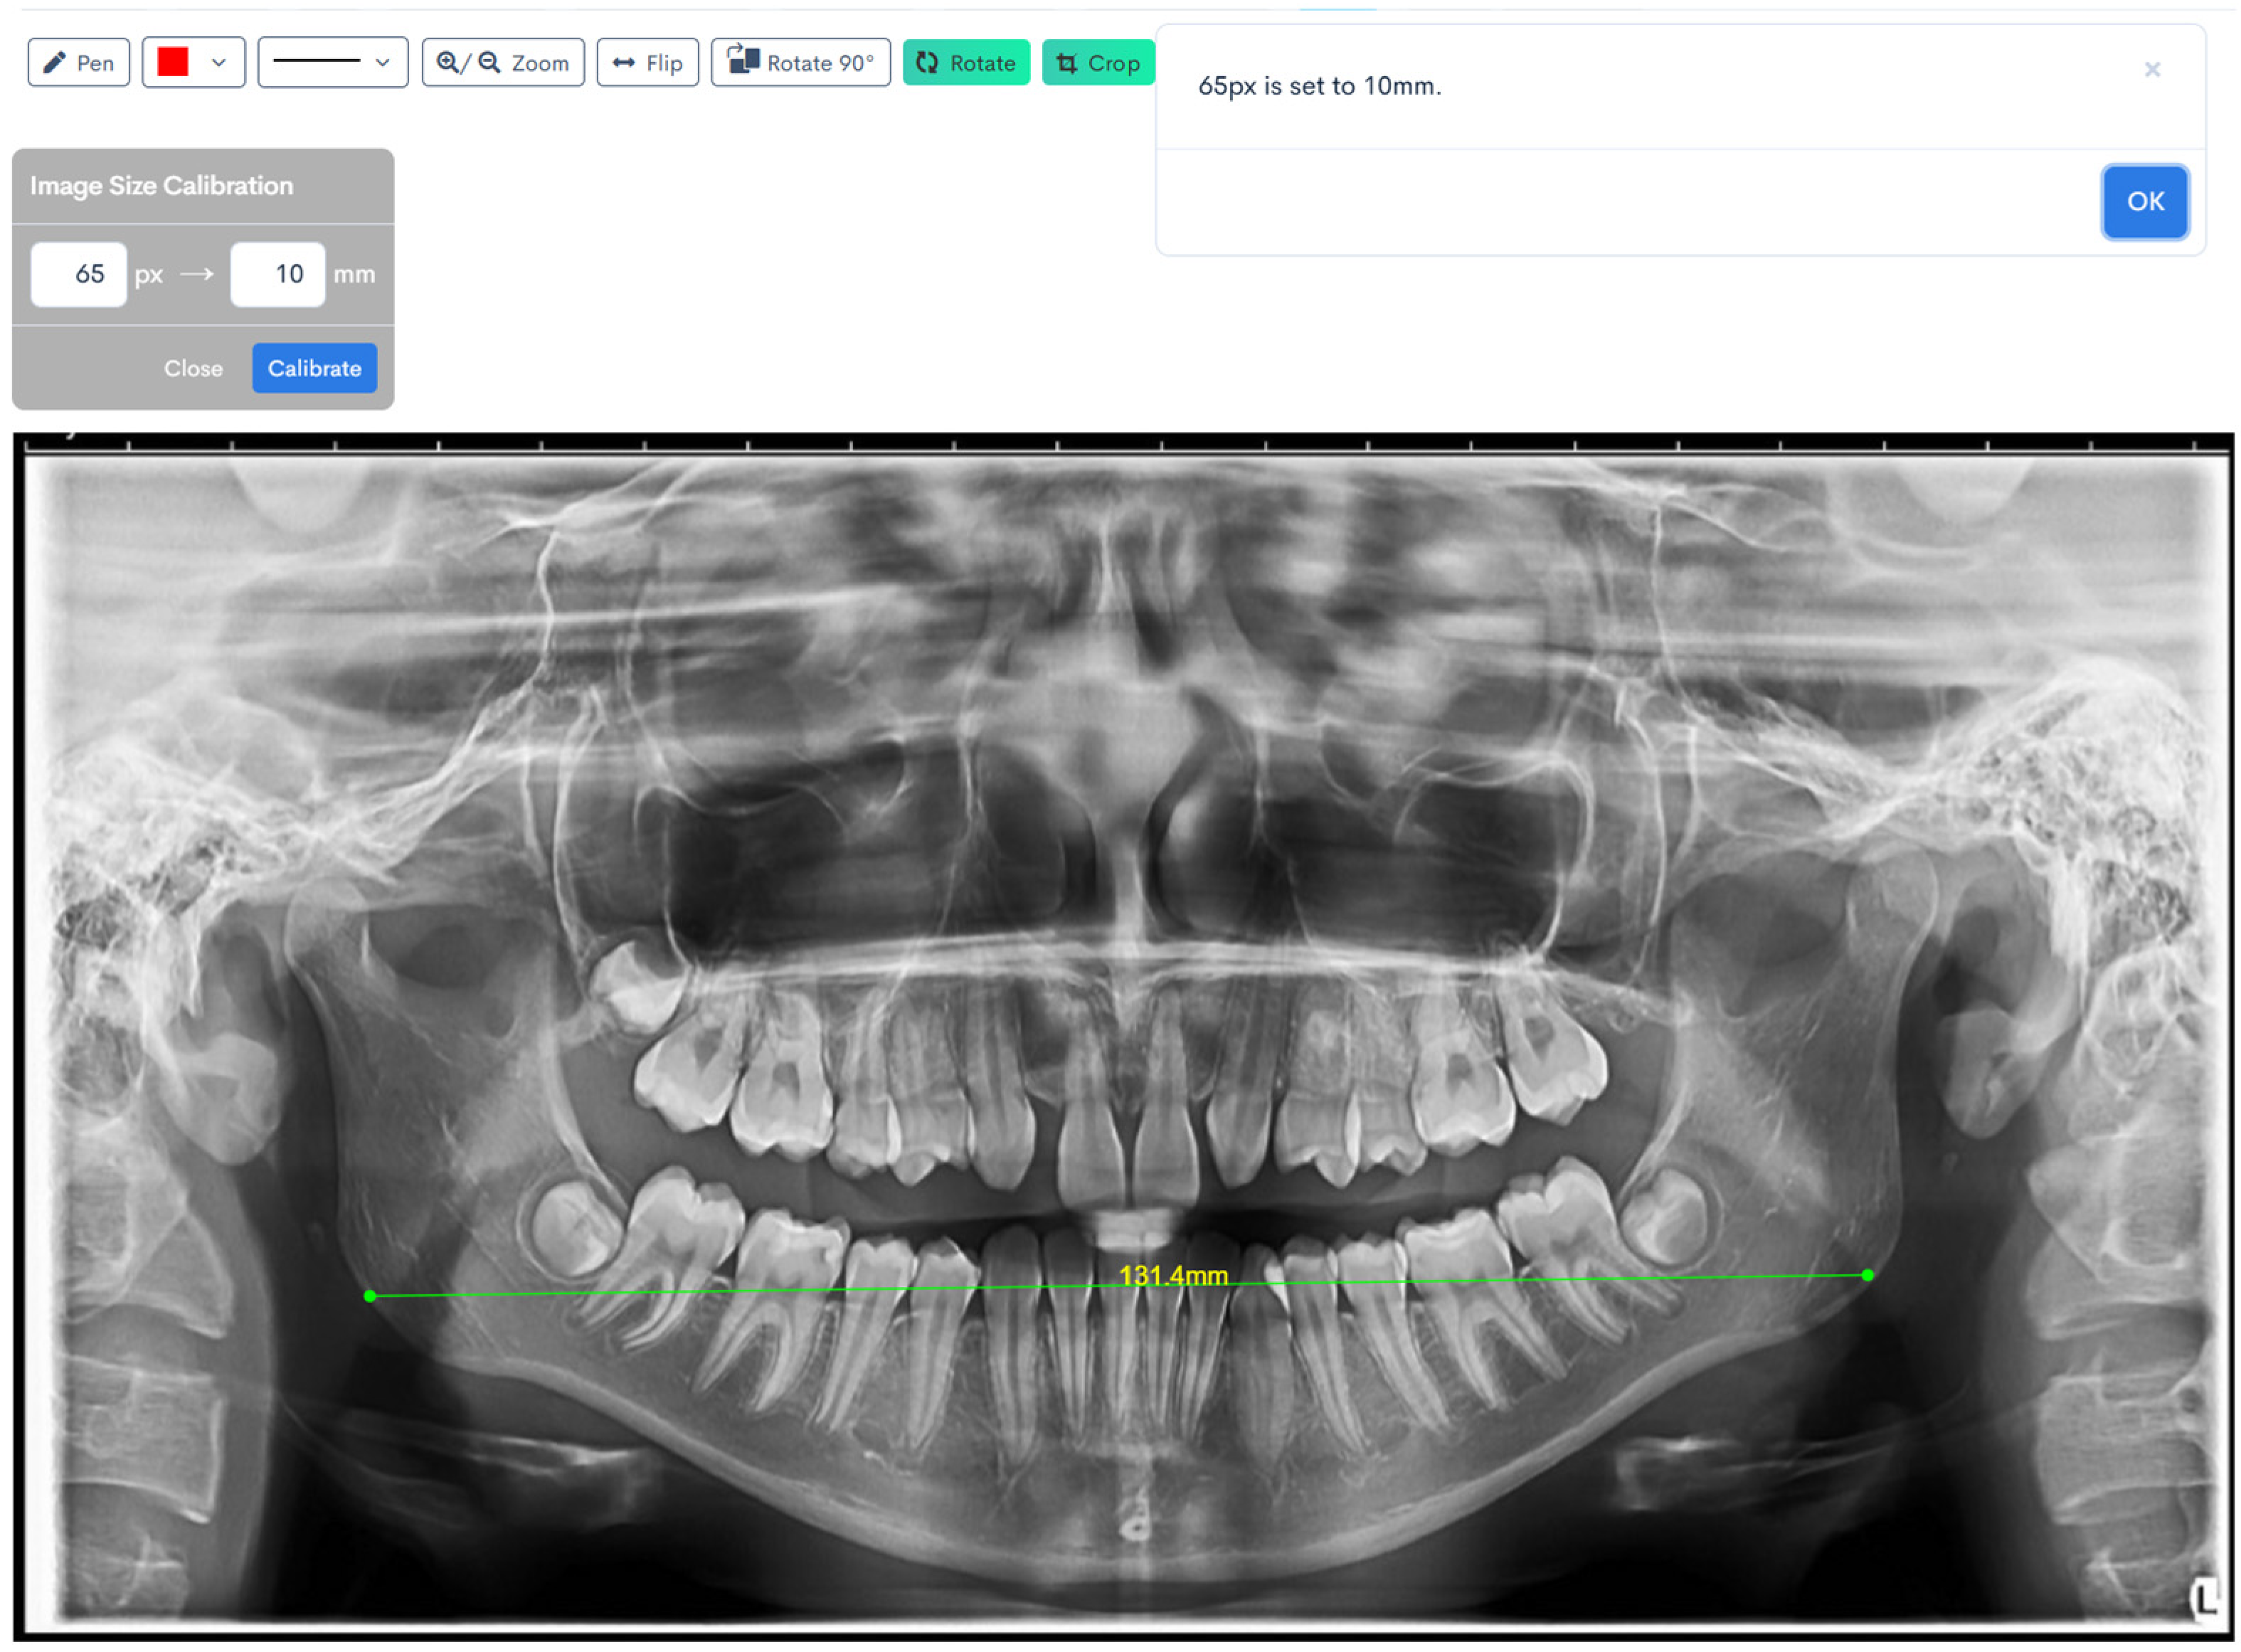

A calibration factor of 65 pixels was applied for all linear measurements performed on the panoramic radiographs [20]. The digital images, saved in JPEG format, were imported into WebCeph, an AI-powered orthodontic analysis platform patented by both the Korean and United States Intellectual Property Offices.

Figure 1, Figure 2, Figure 3, Figure 4, Figure 5 and Figure 6 illustrate the AI-assisted digital measurements exported from the WebCeph software, showing the identification of anatomical landmarks and linear or angular dimensions analyzed in this study.

Digital tracing of bigonial width performed on WebCeph using a panoramic radiograph. The measurement represents the horizontal distance between the right and left gonion points (Go), shown by the green line with an on-screen readout of 131.4 mm (Figure 5).

Figure 5. Bigonial Width Digital Tracing on WebCeph. The green line connects the automatically detected bilateral gonion (Go) points, showing the measured bigonial width (mm). Note: Images represent direct screenshots exported from the WebCeph AI platform. Landmarks and measurement lines were automatically generated and manually verified by the authors.